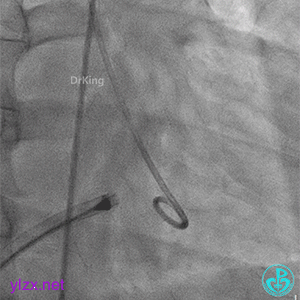

术中造影

结合实际术中造影,为大型膜部瘤室间隔缺损,左室入口直径12.79mm,右室出口直径为6.38mm,选择腰部直径为14的全降解封堵器进行封堵。

建立动静脉轨道

由导丝建立完整动静脉轨道,以便后续手术沿导丝轨道将全降解封堵器系统鞘管送入左心室。